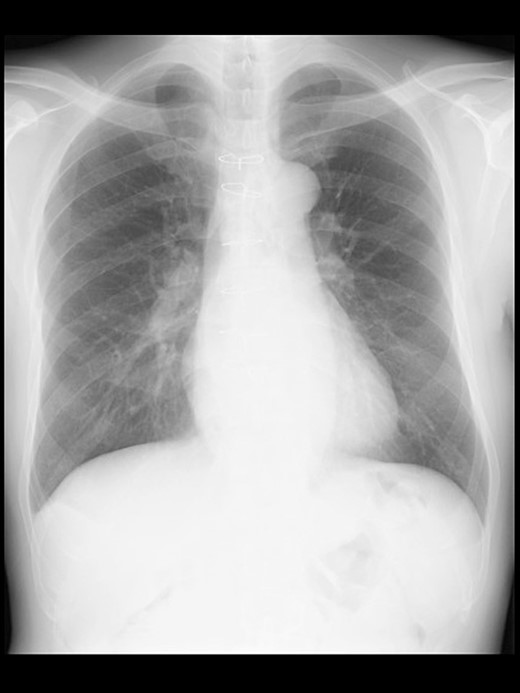

Even though the patient did not receive supplemental oxygen in the ward, SpO2 remained at 98%. Chest radiographs were not taken on the day of surgery. However, a chest radiograph taken in the upright position on postoperative Day (POD) 1 revealed a pneumothorax on the right side (Fig. 2), although he had no respiratory symptoms. Radiographs on PODs 2 and 3 revealed the pneumothorax remaining unchanged (Fig. 3). The patient was discharged from the hospital on POD 3 without any respiratory symptoms. A chest radiograph taken on POD 19 showed no remaining pneumothorax.

A chest radiograph in the upright position on POD 3 showing a residual right pneumothorax (arrowheads).